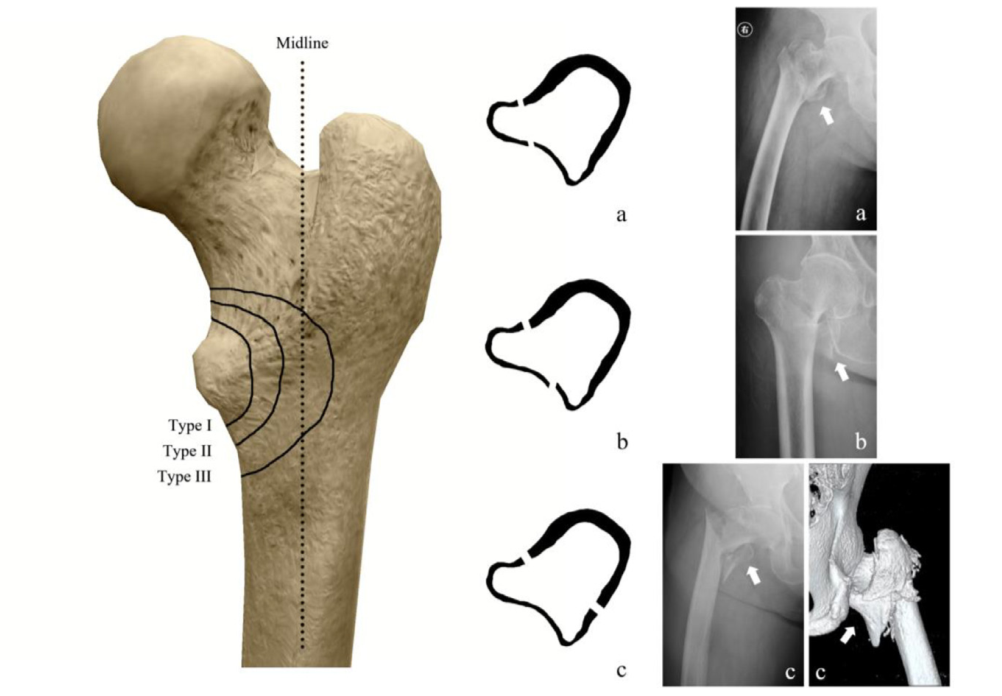

PipkinⅢ型骨折治疗的关键——股骨头毁损三联征!(附案例分析)